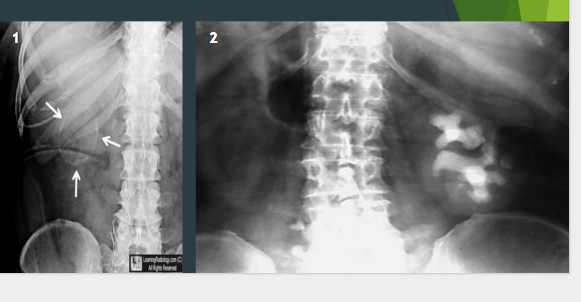

What are these two xrays showing?

Often occurs when?

Ileus

After surgery

What are these xrays showing?

Constipation (full of stuff/stool)